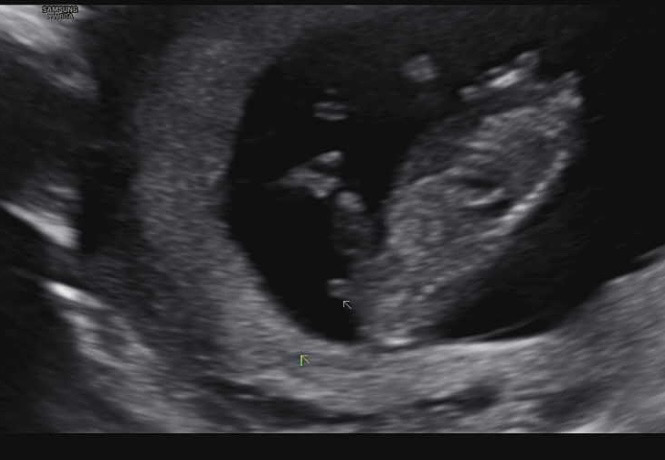

12주 각도법 궁금해용 이거 🌶️일까요

의사쌤이 아들가능성이 좀 더 커보인다고 근데 아직 모르겠다하셨는데 장꾸맘님은 딸각도라고 하시네용!!